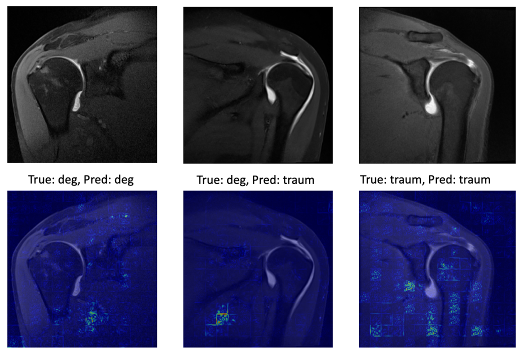

Results: The ViT model achieved an accuracy of 0.72 ± 0.03 with a recall of 0.71 ± 0.09, specificity of 0.72 ± 0.06 and a F1 score of 0.7 ± 0.07. Analysis of the confusion matrix revealed that the model correctly identified an average of 7.2 ± 2.5 traumatic and 7.2 ± 2.48 degenerative cases per validation set. The model maintained consistent performance across different patient subsets, demonstrating robust generalization. Saliency maps do not show a consistent focus on the rotator cuff (Figure 2 [Fig. 2]).

Discussion and conclusions: AI shows potential in supporting the challenging differentiation between traumatic and degenerative rotator cuff tears on MRI. The achieved accuracy of 72% is particularly significant given our stringent inclusion criteria and age-matched cohorts, which presented a challenging diagnostic scenario. Saliency maps were utilized to ensure explainability, the given lack of consistent focus on rotator cuff tendons hints towards underappreciated aspects in the differentiation. These findings establish a foundation for developing AI-assisted diagnostic tools in musculoskeletal radiology, potentially enhancing both diagnostic accuracy.